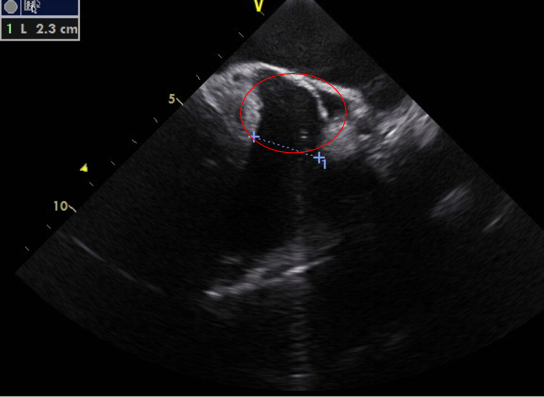

通过采集以下切面显示二尖瓣瓣叶各扇叶。(1)胸骨旁左心室长轴切面,显示A2、P2(图5A);(2)二尖瓣水平短轴切面,显示整个前后叶(图5B);(3)心尖四腔心切面,显示A2、P2(图6A);(4)心尖长轴切面,显示A2、P2(图6B);(5)心尖二腔心切面,显示A1、P3(图7A);(6)心尖二尖瓣交界处长轴切面,显示P1、A2、P3(图7B)。经胸超声心动图通过上述切面评价MR的机制、程度以及部位,并确定瓣膜运动异常的扇叶。

图 5 经胸二维超声心动图显示二尖瓣瓣叶各扇叶 A. 胸骨旁长轴切面,显示二尖瓣前叶 A2 处、二尖瓣后叶 P2 处;B.二尖瓣水平短轴切面,显示二尖瓣前叶 A1、A2、A3 及二尖瓣后叶 P1、P2、P3